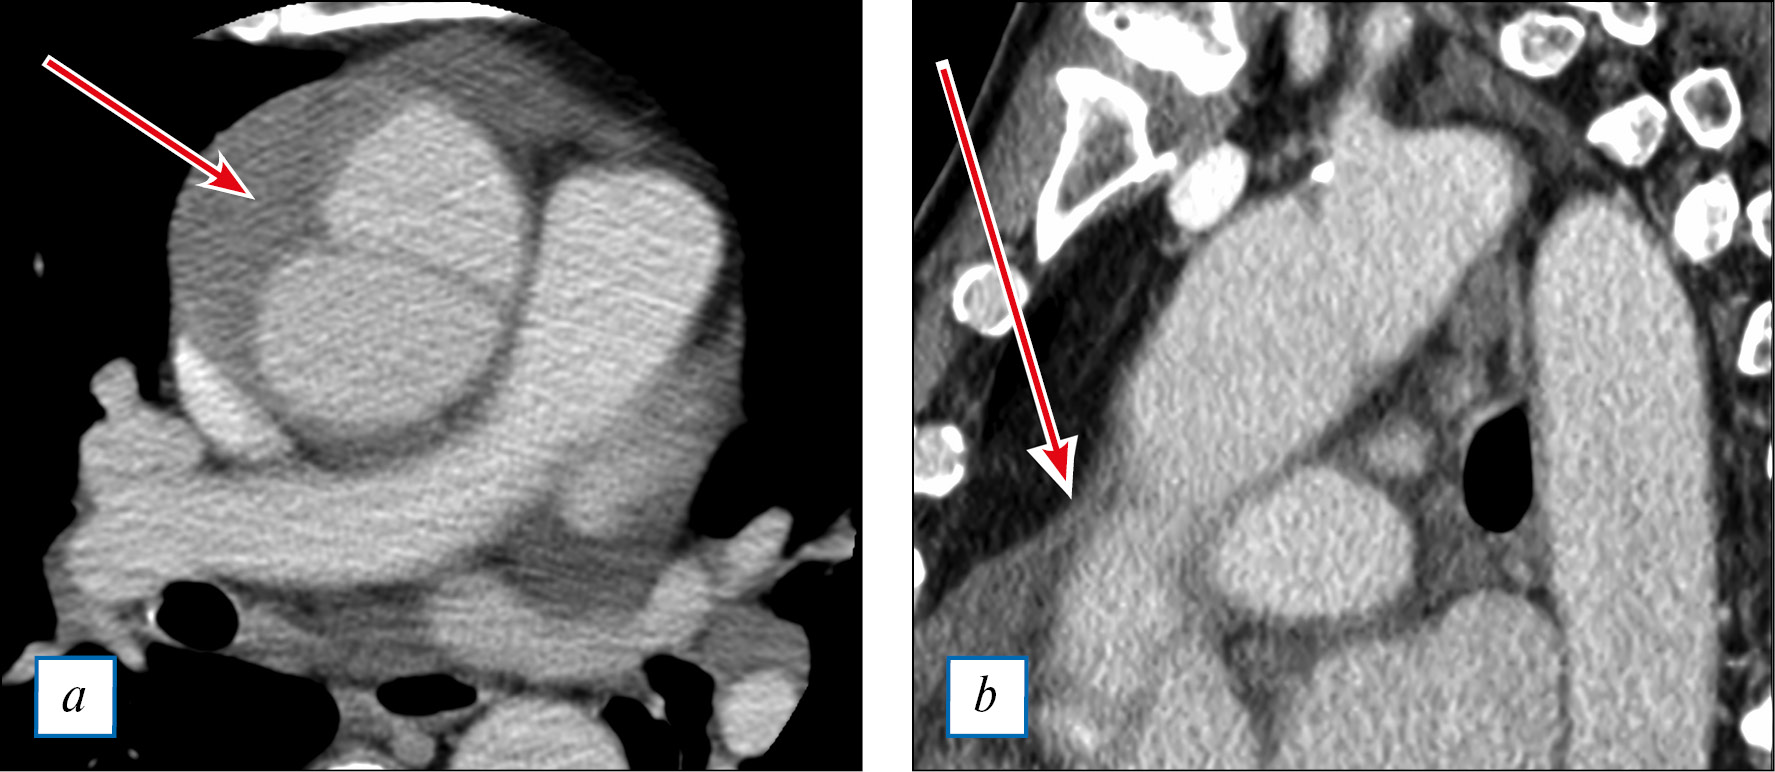

Компьютерно-томографическая (КТ) аортография: в проксимальном отделе восходящей аорты визуализируется надрыв интимы с формированием расслоения, которое распространяется дистально по левой поверхности дуги до уровня отхождения левой подключичной артерии без перехода на ее устье, слепо заканчивается по левой нижней стенке; визуализируется переход расслоения на ствол левой коронарной артерии (рис. 2). Расслоение восходящей аорты типа А по Стенфордской классификации.

Рис. 2. Тот же пациент: КТ-аортография.

Примечание. a — поперечный срез восходящего отдела аорты (стрелкой обозначен канал расслоения аорты); b — продольный срез восходящего отдела аорты (стрелкой обозначен канал расслоения аорты).

Fig. 2. The same patient: CT-aortography.

Note. a — cross-section of the ascending aorta (the canal of aortic dissection is marked with an arrow); b — longitudinal section of the ascending aorta (the canal of aortic dissection is marked with an arrow).